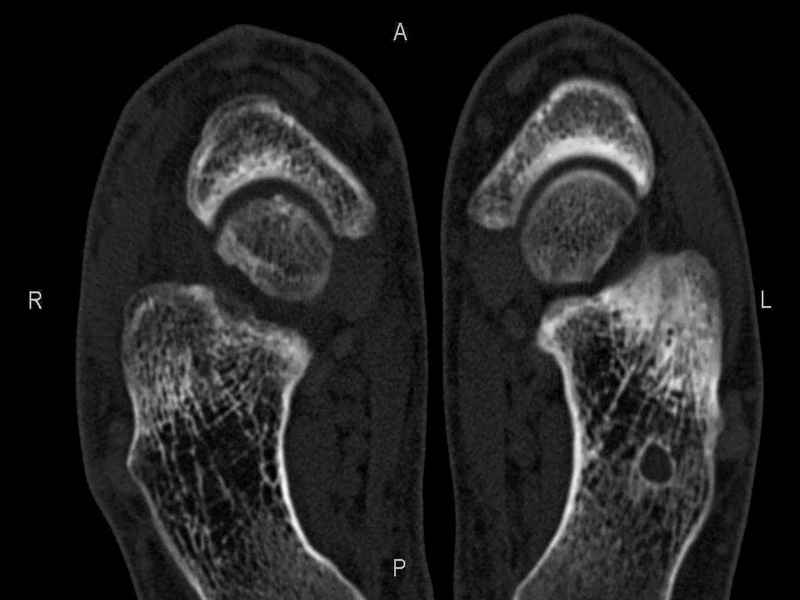

На СКТ картина рассекающего остеохондрита блока

таранной кости, киста шейки таранной кости с признаками импрессии суставной поверхности. А

также - разрастания переднего края б\берцовой кости сопровождающиеся клиникой импиджмент

синдрома.